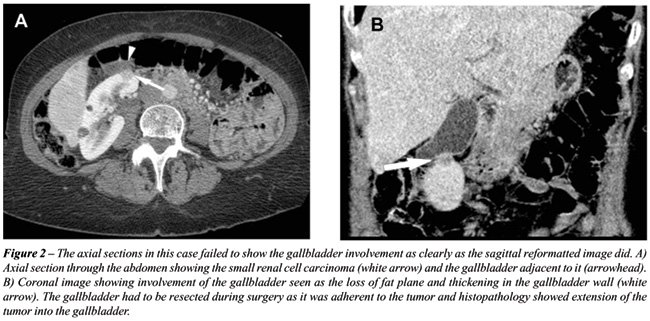

With the rapid acquisition of multiple simultaneous slices and thin-section reformatted coronal and/or sagittal images, the 64-slice CT scanner provides excellent detail in demonstrating local extension to the bowel and retroperitoneum (see Figures-2, 3, 5, 6 and 7). Multiplanar three-dimensional reconstruction techniques including volume rendering, maximum intensity projection and shaded surface display provide comprehensive information about the relationships and possible involvement of vascular structures in renal neoplasms.